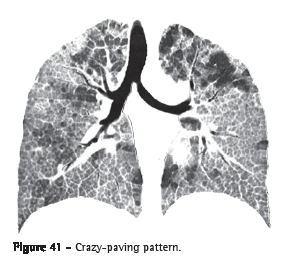

Crazy-paving pattern (padrão de pavimentação em mosaico)The crazy-paving pattern presents superimposition of ground-glass

opacities, interlobular lines and thickened interlobular septa (Figure 41).

The interface between the normal and the affected lungs tends to be well-delimited in this pattern of pulmonary lesion. This pattern was initially identified in patients with pulmonary alveolar proteinosis, but it can also be seen in other diffuse pulmonary diseases in which the interstitial and alveolar compartments are affected (e.g., pulmonary hemorrhage).(1,2,64)